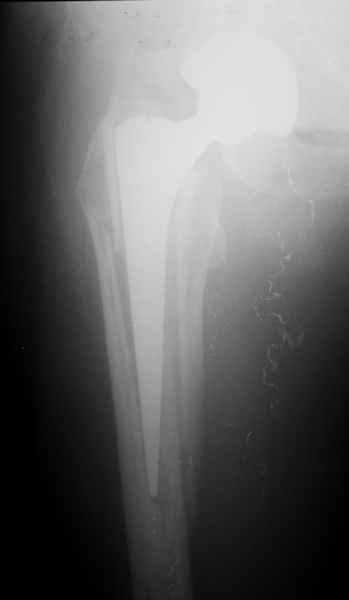

2. Применение ножки дистальной фиксации, мы отдаем предпочтение ножке Вагнера с фиксацией проксимального отдела на ножке. Более травматичное вмешательство, но при стабильной фиксации ножки реабилитация идет в обычном режиме.

Хочется показать два подобных случая, П-ка З. 72 лет и п-т Г. 80 лет. Сразу принимаю замечание, что это были ножки цементной фиксации, просто под руками не было бесцементника.

Пациента удалось осмотреть недавно. Достигнутый результат сохраняется. Перелом бедра сросся. Конечность опорная и безболезненная, ходит без трости. Ножка, похоже, реинтегрировалась, как и надеялись. Снимки и фото в приложении. Комментарии приветствуются.

Надо ли что-то делать дальше, как полагаете? Убрать винты? Убрать "удлинитель ножки"? Или оставить все, как есть? Спасибо заранее.